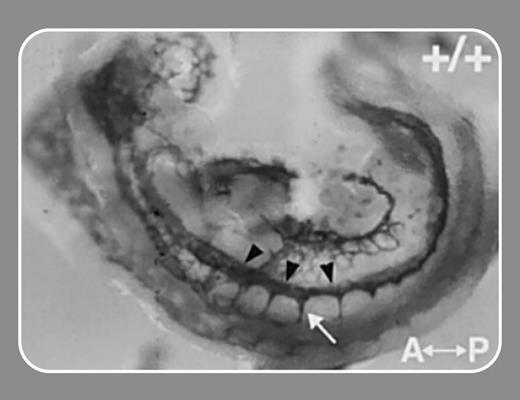

In this issue, Kearney and colleagues (page 4527) use Vegfr-1 null mice and the elegant technique of confocal time-lapse imaging to examine the dynamics of vascular sprout formation in order to test a role for VEGFR-1 in VEGF-induced endothelial cell migration. Their experiments reported here do indeed show decreased sprouts and reduced migration rate in differentiated Vegfr-1-/- vessels. Perhaps the most surprising finding is the capacity of an sflt-1 transgene to rescue the mutant phenotype. The implication is that sflt-1 can bind local VEGF-A and alter the concentration gradient of this growth factor, which drives both sprouting and endothelial cell migration.